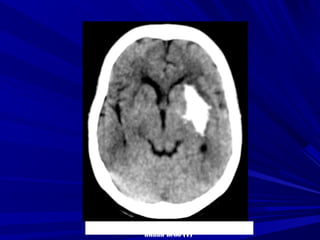

Fogging effect: Hiện tượng đồng đậm độFogging effect: Hiện tượng đồng đậm độ

vùng nhồi máu ở ngày 14-21 do tăng thựcvùng nhồi máu ở ngày 14-21 do tăng thực

bào hoặc xuất huyết vi thể, khi đó vùngbào hoặc xuất huyết vi thể, khi đó vùng

nhồi máu rất khó nhận thấy.nhồi máu rất khó nhận thấy.

Một số trường hợp có hiện tượng tăngMột số trường hợp có hiện tượng tăng

quang do xuất huyết trong vùng nhồi máuquang do xuất huyết trong vùng nhồi máu

vào sau ngày thứ ba.vào sau ngày thứ ba.

Fogging EffectFogging Effect

24 giờ 11 ngày 4 tháng